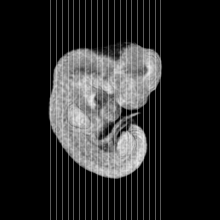

Carnegie Stage 15 (33 post-ovulatory days)

Most embryos at stage 15 are approximately 33 postovulatory days old and measure 7-9 mm in length. Distinguishing criteria for this stage include the appearance of nasal pits and hand plates. The lens vesicles are closed.

MRI Slice Selector

Mouse: click on a line below to select a view

Finger: tap a line below with a very light touch